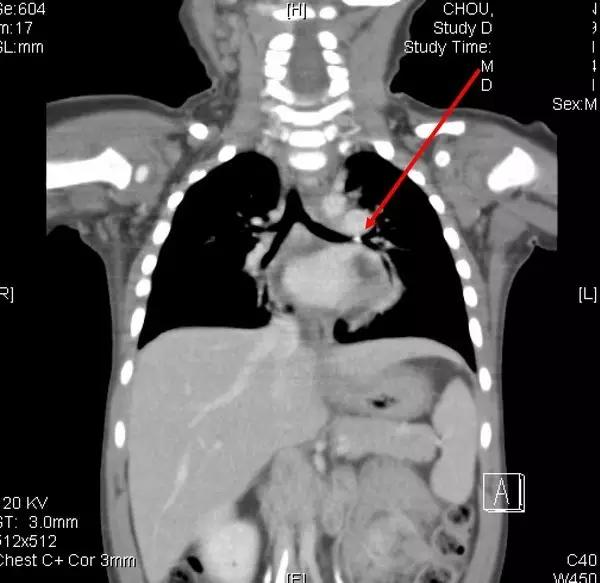

2岁的小光咳了2个月,原本以为是感冒,吃了不少感冒药,因为一直不会好,只好带到大医院,评估安排做进一步的检查。医师在检查之后,竟然用呼吸道内视镜从气管内夹出了一个小玩具车的小轮轴。仔细回想,爸爸妈妈才想到2个月前,小光把小玩具车放到嘴巴里,负责照顾的爷爷虽然手忙脚乱紧急抢下玩具车,却没有发现玩具车的小轮轴不见了。